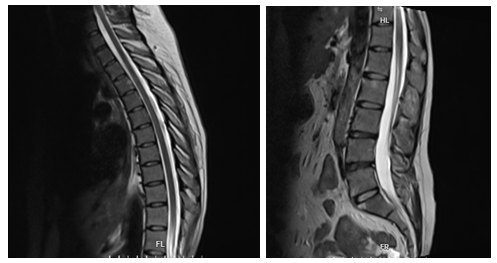

Hình ảnh chụp cộng hưởng từ cột sống ngực và cột sống lưng của người bệnh - Ảnh BSCC

Người bệnh được chỉ định chụp cộng hưởng từ (MRI) cột sống lưng, cột sống ngực và khớp cùng chậu, xét nghiệm cho thấy người bệnh mang kháng nguyên HLA-B27 dương tính. Người bệnh được chẩn đoán: Viêm cột sống dính khớp, một bệnh tự miễn mạn tính thuộc nhóm bệnh lý cột sống – khớp có thể gây biến dạng, dính khớp, tàn phế nặng nếu không được điều trị kịp thời và đúng cách.